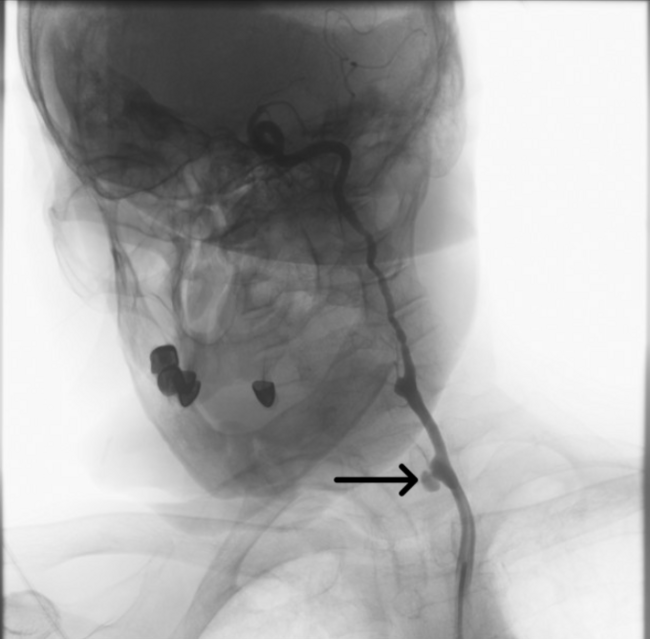

Video 1. Active contrast extravasation from the left ınternal carotid artery. Digital subtraction angiography demonstrated active contrast extravasation originating from the distal segment of the left internal carotid artery, consistent with carotid blowout syndrome. The bleeding point was clearly visualized with pooling of contrast adjacent to the tumor-invaded arterial wall.